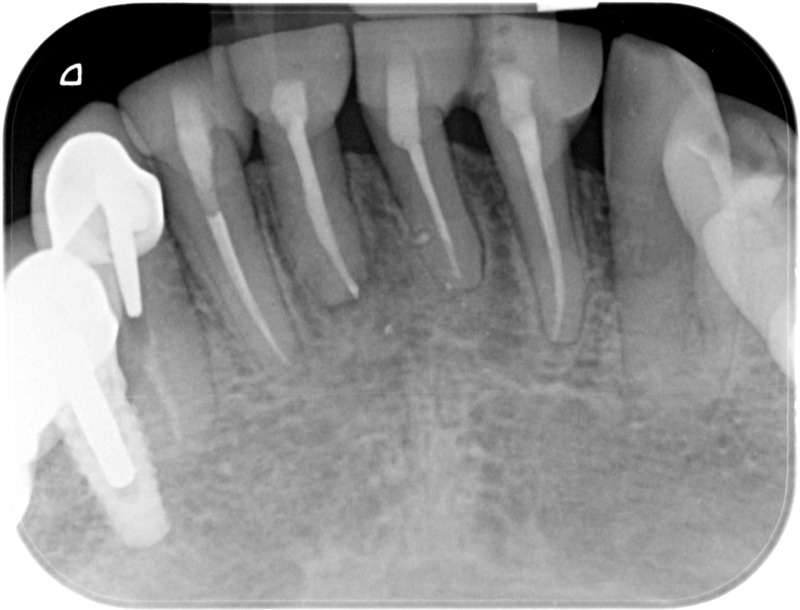

• Traitement endodontique : Sous anesthésie locale et à travers la protection d’un champ opératoire nous accédons à la pulpe de la dent à soigner, puis aux canaux de ses racines que nous devons désinfecter. Ce soin nécessite l’élimination complète de la source de contamination (souvent la carie) parfois sous une ancienne reconstitution ou une couronne qu’il faut alors retirer. Une fois le nettoyage et la mise en forme des canaux réalisés, nous les obturons de façon hermétique avec un ciment et un matériau thermoplastique appelé Gutta Percha. Ceci afin d’empêcher une nouvelle prolifération bactérienne et d’assurer le maintien de la dent dans ses structures de soutien (ligament parodontal et os alvéolaire). L’ouverture effectuée au centre de la dent sera d’abord refermée avec un pansement provisoire avant d’envisager ensemble la reconstitution d’usage : un composite, un inlay-onlay ou une couronne.

Avant